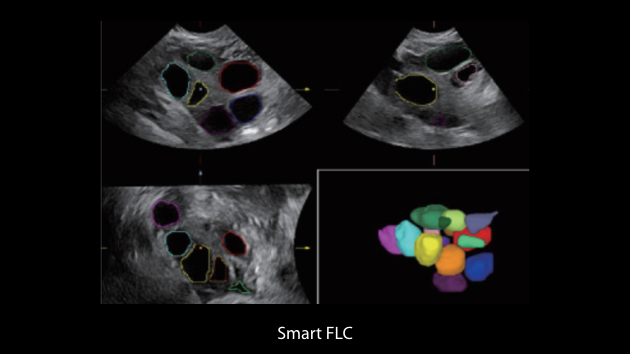

Nuewa I9 Elite Edition ├© progettato appositamente per l'assistenza sanitaria a donne e neonati e offre un'esperienza innovativa sviluppata sulla base di conoscenze approfondite relative a scenari clinici complessi, per risposte accurate e tempestive, nonch├® un'efficienza e un'esperienza utente eccezionali